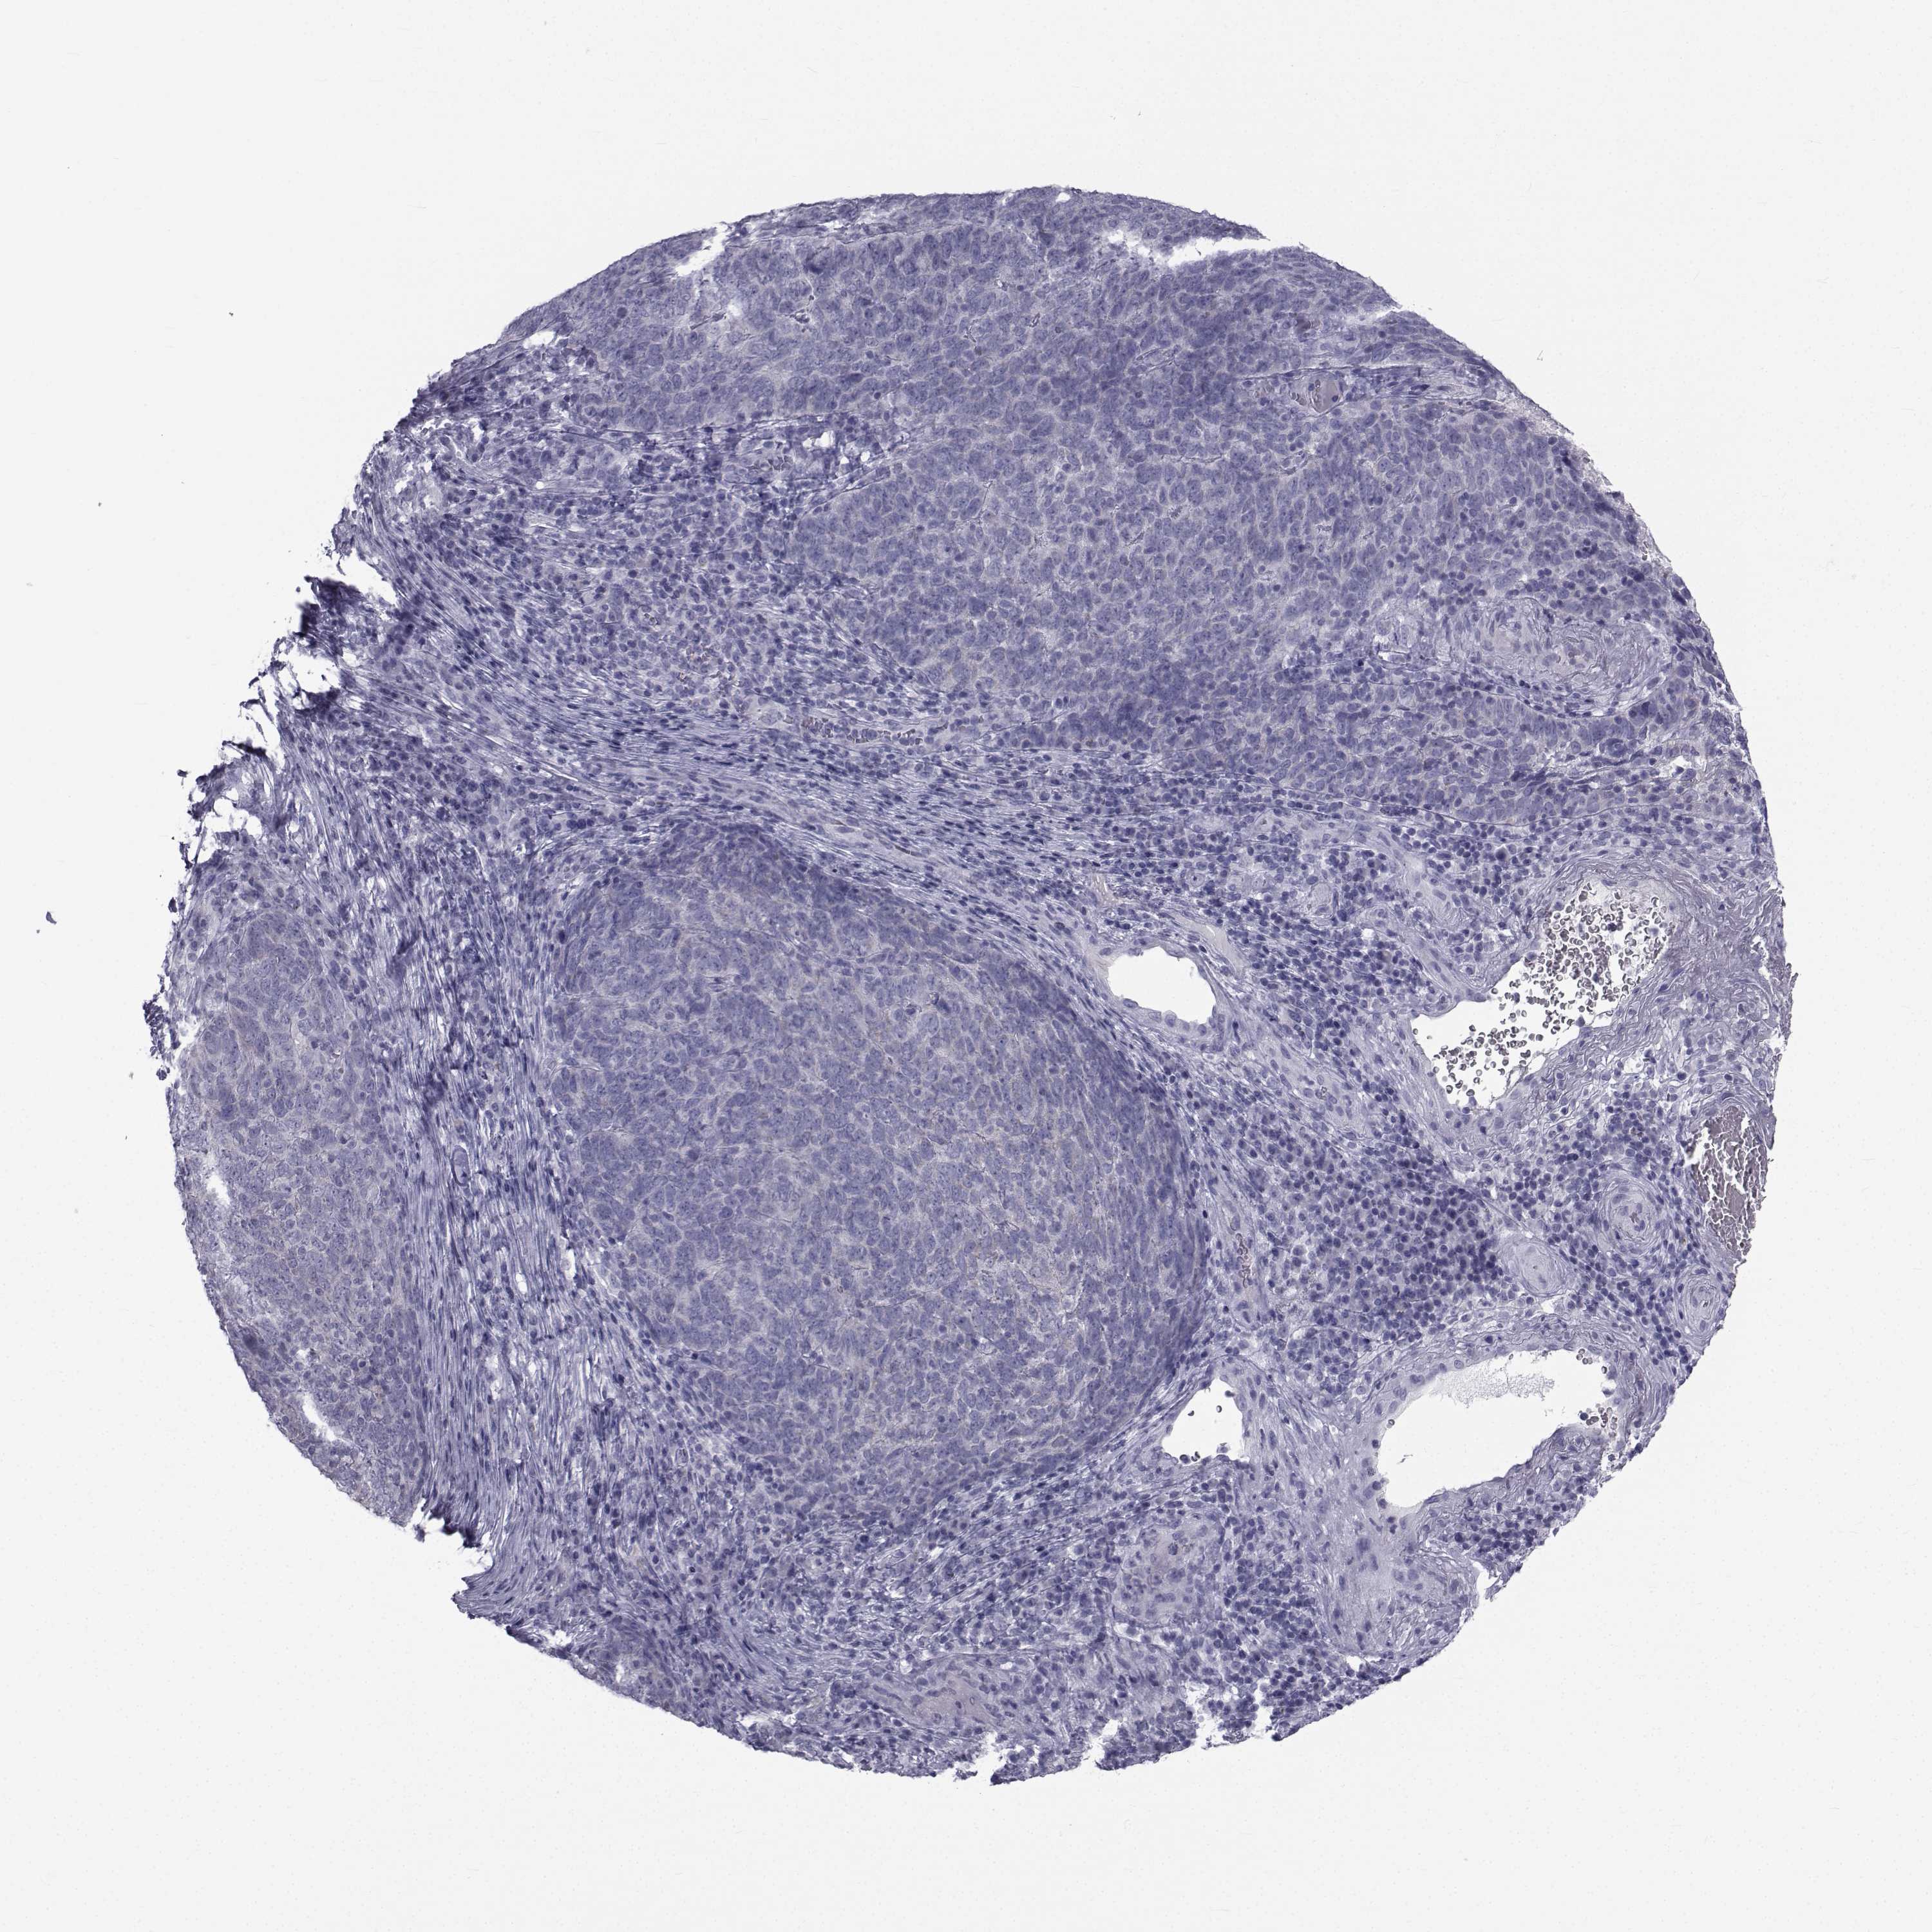

Basal cell and squamous cell cancer

SKIN CANCER - Protein expressioni

A mouse-over function shows sample information and annotation data. Click on an image to view it in a full screen mode. Samples can be filtered based on level of antibody staining by selecting one or several of the following categories: high, medium, low and not detected. The assay and annotation is described here.

Antibody stainingi

Antibody staining in the annotated cell types in the current human tissue is reported as not detected, low, medium, or high, based on conventional immunohistochemistry profiling in selected tissues. This score is based on the combination of the staining intensity and fraction of stained cells.

Each image is clickable and will lead to virtual microscopy that enables deeper exploration of all samples and also displays staining intensity scores, fraction scores and subcellular localization as well as patient and tissue information for each sample.

Antibody HPA044393

Antibody HPA053673

Antibody CAB009818

Staining

High

Medium

Low

Not detected

Intensity

Strong

Moderate

Weak

Negative

Quantity

>75%

75%-25%

<25%

None

Location

Nuclear

Cytoplasmic/membranous

Cytoplasmic/membranous,nuclear

Squamous cell carcinoma, NOS

Basal cell carcinoma